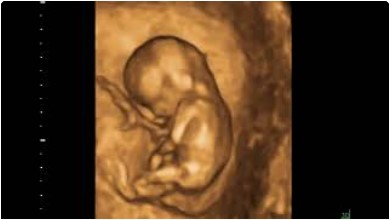

また見て頂いた4Dエコーを自身のスマートフォンで閲覧できる「エコー動画館」というシステムを導入しており、診察後に簡単にエコー画像、動画をご覧いただくことが可能です。是非、ご家族とご一緒にエコー画像、動画をご覧いただければと思います。

- 超音波検査(赤ちゃんの発育の確認)

- 超音波検査(胎盤位置や頸管長の確認)

胎児超音波を通して、皆様が安心してマタニティー・ライフを送れるように精一杯頑張らせて頂きます。